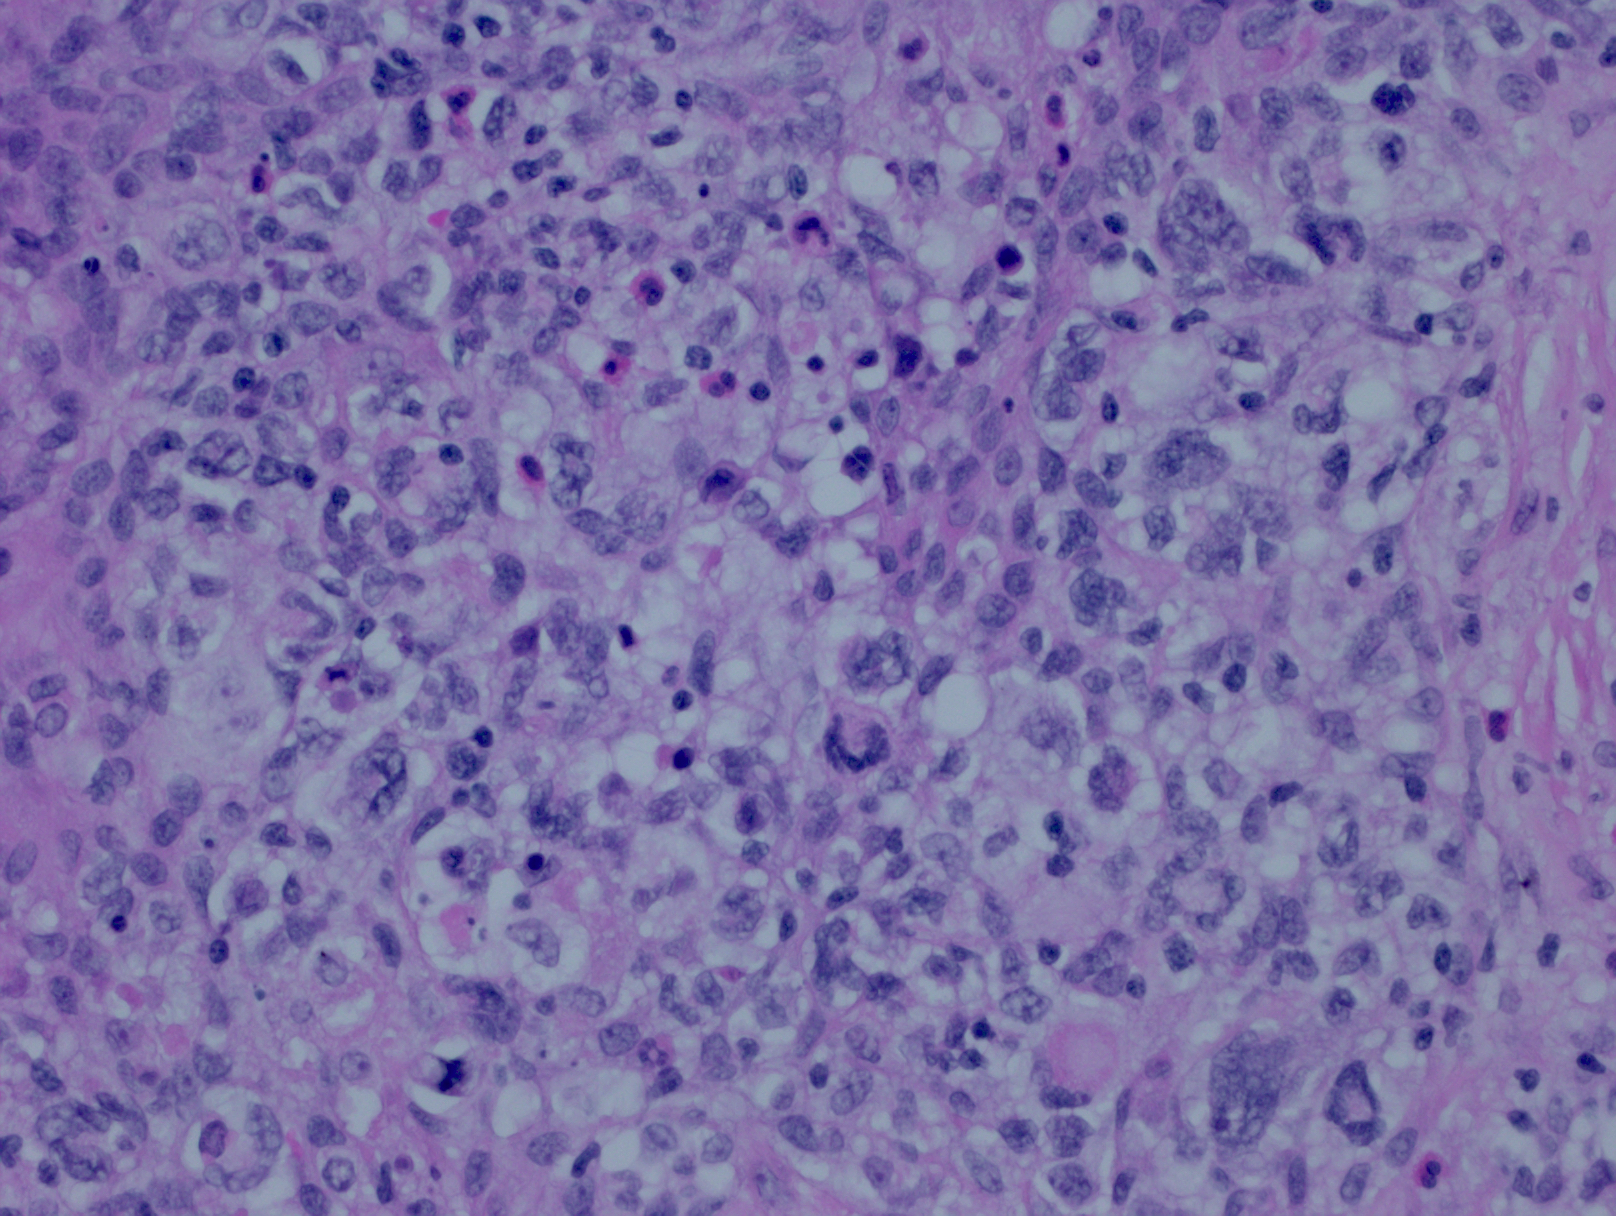

肿瘤由多形性大细胞组成并伴一定程度纤维化。可成片状生长,类似原发纵隔大 B 细胞淋巴瘤或弥漫大 B 细胞淋巴瘤;但也可散在侵润,类似经典霍奇金淋巴瘤。这两种生方式可见于同一病例的不同区域。

细胞形态多样,中心母细胞、免疫母细胞和 HRS 细胞包括腔隙性样细胞。有少量炎性背景细胞如散在的嗜酸细胞、组织细胞和小淋巴细胞。